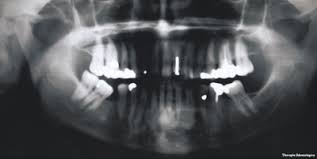

Pediatric Facial Swelling A Guide To Radiologic Diagnosis

Pediatric Facial Swelling A Guide To Radiologic Diagnosis from slidetodoc.com